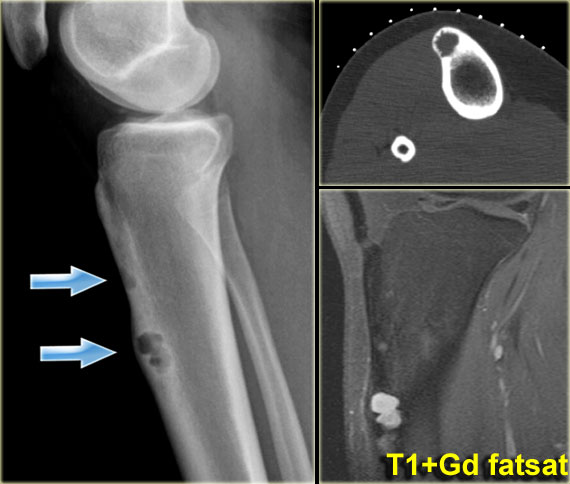

Chondrosarcoma arising from osteochondroma

Chondrosarcoma (8)

On the left a patient with a calcified mass arising from the proximal fibula.

The size of the lesion and the high uptake on the bone scan suggest that this is a chondrosarcoma.

Peripheral chondrosarcomas can arise from osteochondromas.

Measuring the cartilage cap will help in distinguishing benign osteochondromas from chondrosarcomas.

With 2 cm used as a cutoff for distinguishing benign osteochondromas from chondrosarcomas, the sensitivities and specificities were 100% and 98% for MR imaging and 100% and 95% for CT, respectively (3).

Chondrosarcoma (8) continued

On the left the axial T2 WI.

Notice that the tumor arises from an osteochondroma, which is shown in the center part of the image (arrow).

Chondrosarcoma (9)

On the left a patient with a broad-based osteochondroma with extension of the cortical bone into the stalk of the lesion.

Notice the lytic peripheral part with subtle calcifications.

This part corresponds to a zone of high SI on T2-WI with FS on the right.

This represents a thick cartilage cap.

This is an example of progression of an osteochondroma to a peripheral chondrosarcoma.